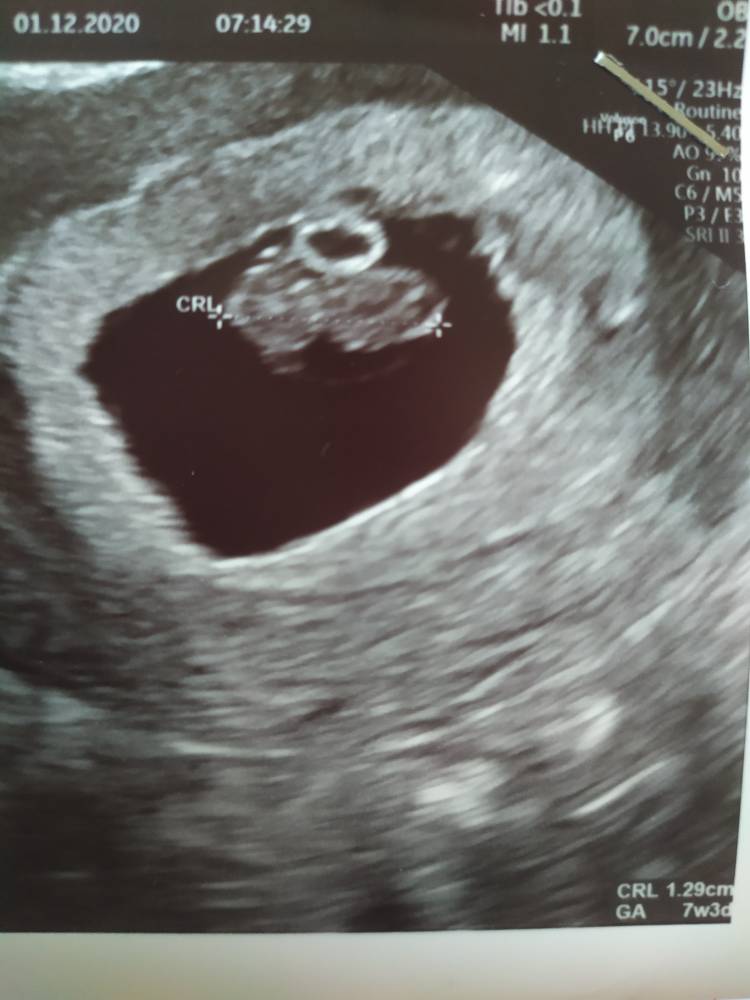

Moja historia kończy się właśnie dzisiaj. Zarodek jest i cały czas tam był. Ta pseudopołożna zmierzyła coś co było w szyjce a nie nawet w macicy W piątek być może z [emoji173] ale niestety się zatrzymało. Możliwe że dzisiaj bo zarodek mierzy idealnie na 7+6. Czekam na poronienie. Serce mi się rozpadło na milion kawałków. Czuje ze nigdy się nie pozbieram Życzę wam wszystkim powodzenia.